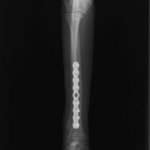

脛骨骨折 : 症例1 | 症例2 | 症例3 | 症例4 | 症例5

当院ではAdvanced Locking plate system(ALPS)と、Locking compression plate system(LCPS)という骨接合法で骨折症例の治療を行っています。

トイプードル 右遠位橈尺骨短斜骨折のALPSによる内固定